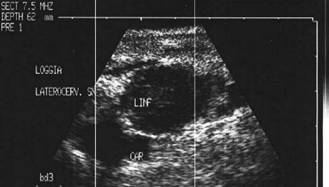

Femeie de 29 ani. Linfonodul in regiunea

laterocervicala dreapta ( 7x12x23mm, 1 cc) in neoplazie papilara a tiroidei. Structura

parenchimatoasa, neomogenea, cu margini

nete, cu absenta hilului.Examen citologic: metastaza de neoplazie papilara.

Lob drept,

proiectie trasversala si longitudinala

Aceeasi pacienta. Nodul de consistenta dura in lobul

drept spre istm.

Ecografia: nodul cu margini indistinte care deformeaza marginea anterioara a glandei,

parenchimatoasa, neomogena, hipoecogena. Prezenta de linfonodi laterocervicali.

Ctoaspiratie: carcinom papilar.